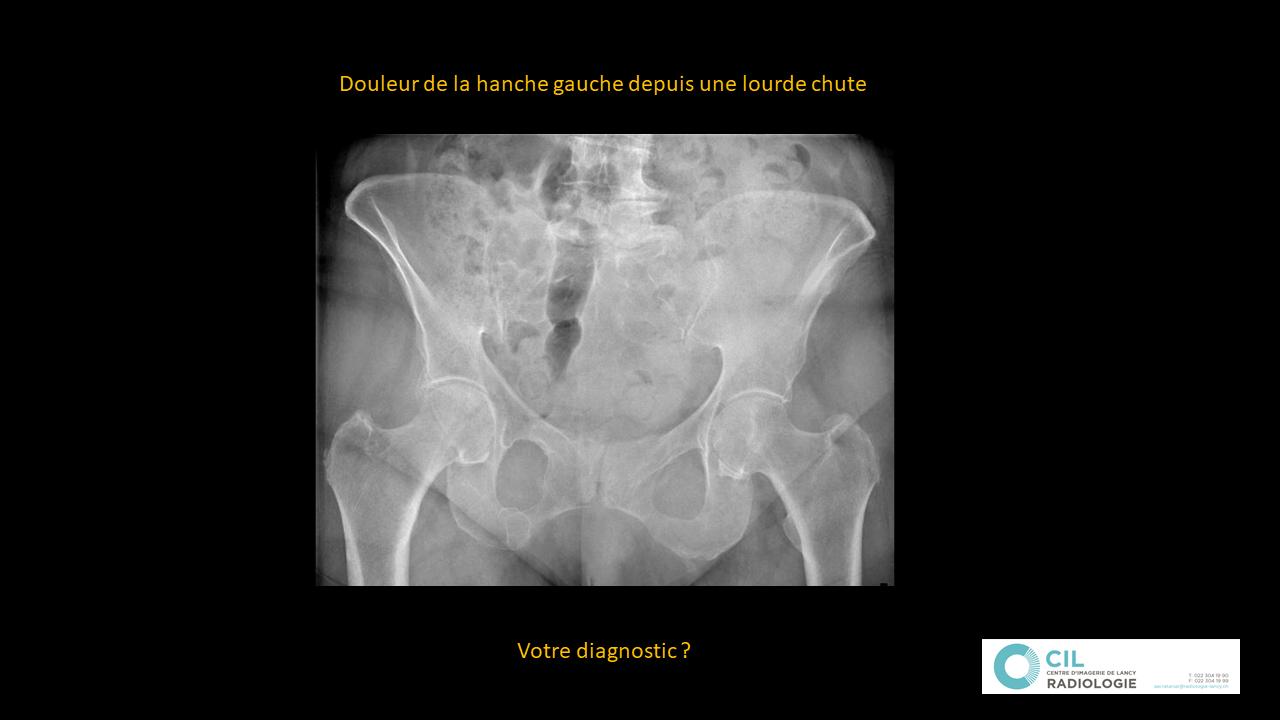

Musculosquelettique